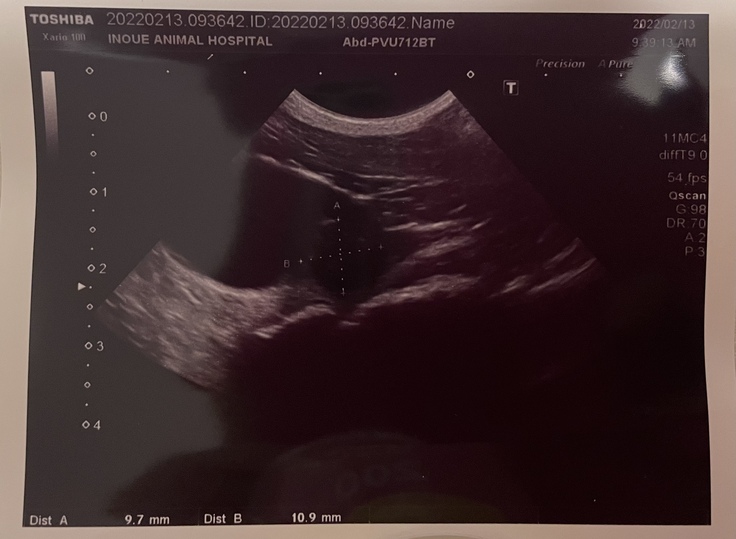

・2022年2月13日

再度エコー検査。

ほし膀胱癌腫瘍のエコー写真

2022年2月13日撮影

膀胱移行上皮癌、再発確定

この日は今後の選択肢を聞いて、帰宅。